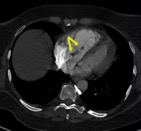

В статье представлен случай успешного хирургического лечения тромбоэмболии легочной артерии у пациентки с высоким риском ранней сердечной смерти на фоне парадоксальной эмболии, осложненной острым нарушением мозгового кровообращения. Криптогенное острое нарушение мозгового кровообращения в комбинации с тяжелой прогрессирующей правожелудочковой недостаточностью на фоне ТЭЛА обусловливает серьезные трудности при принятии решения в отношении тактики лечения у данных больных. Внутрисердечная локализация тромбоэмбола, угрожаемая развитием не только рецидива тромбоэмболии легочной артерии, но и парадоксальной эмболии требует незамедлительного выполнения комплекса дифференциально-диагностического обследования, направленного на верификацию патофизиологического механизма развития заболевания, что во многом определяет эффективность проводимого лечения. Анализ доступных литературных данных, приведенный в работе, а также анализ клинического случая позволяют выработать тактический алгоритм в этой группе пациентов и определить показания к открытому оперативному вмешательству.